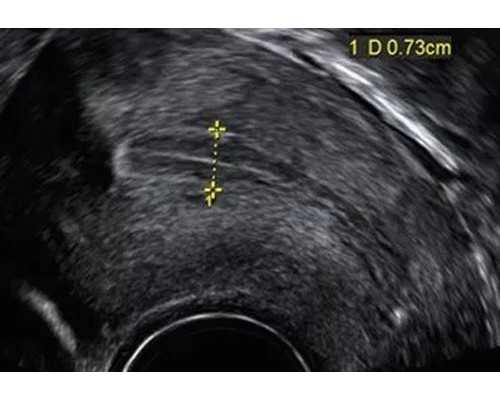

正规的检测机构是需要满足一定条件才能安排检测的,如果满足不了条件不能进行预约。满足条件之一就是宝妈必须孕满7周且胚芽长10mm以上,还需要进行B超检测,以B超检测报告为准。如有一家检测机构没有问你任何情况就帮你预约检测,宝妈一定不要去,肯定是假的检测机构 。

- 7周要求:孕妇的胚芽 (CRL) 需达到9mm以上或孕囊 (GS) 需达到35mm,且见到心管搏动,才可进行测试。

七周胎囊长形香港验血女孩

顾名思义,香港验血检测就是通过抽取孕妈妈们的血液,然后进行检测宝宝性别的,这是一种不同于传统B超检测宝宝性别的先进检测技术,在孕妈妈们肚子里的小宝宝胚芽长度长到满足十毫米或者以上的长度就可以进行,一般也就是孕妈妈们在怀孕满够七周的时间,肚子里的宝宝就会生长发育到满足此项要求,所以这个时候孕妈妈们就可以通过验血来检测自己宝宝的性别了,所以香港验血检测宝宝性别所需要的孕期时间是最短的,这也是它的非常大的一个优势所在。